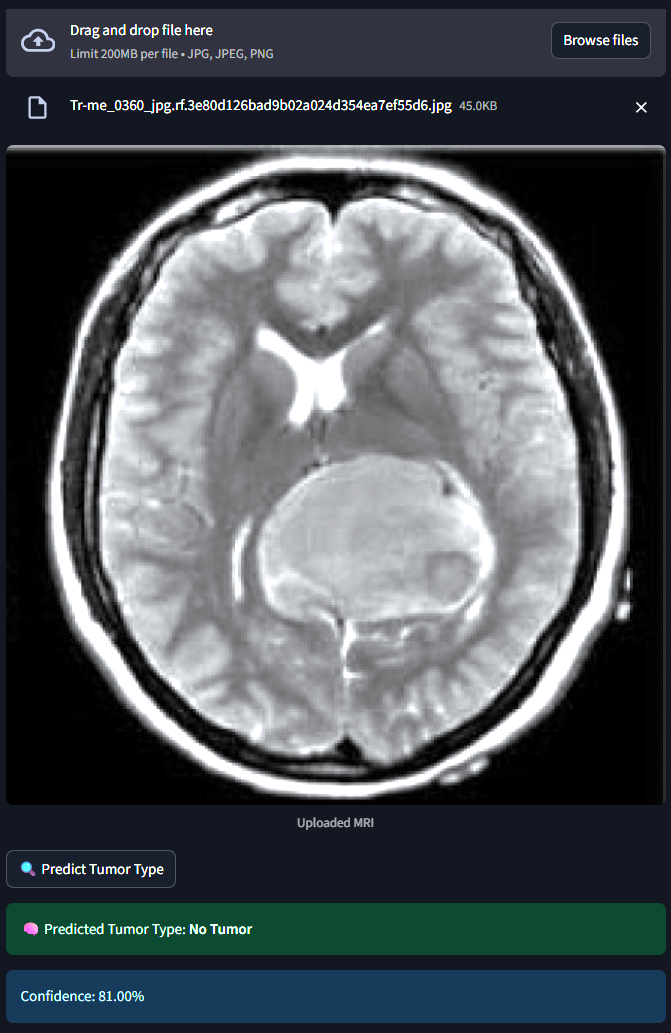

The system classifies MRI brain scans into one of four categories - Glioma, Meningioma, Pituitary Tumor or No Tumor. It uses both a Custom Convolutional Neural Network (CNN) and MobileNetV2 Transfer Learning for classification. An interactive Streamlit web app allows users to upload MRI images and receive real-time tumor predictions with probability scores.

1) Dataset :- 2,443 MRI images labeled and categorized by medical experts. 2) Preprocessing :- Used ImageDataGenerator for rescaling, rotation, zoom and flipping to augment limited data. 3) Model 1 (Custom CNN) :- Built from scratch with 3 convolutional layers, dropout and softmax classification. 4) Model 2 (MobileNetV2) :- Fine-tuned transfer learning model using pretrained ImageNet weights. 5) Training :- Used callbacks like EarlyStopping and ModelCheckpoint to optimize training and avoid overfitting. 6) Evaluation :- Tracked model performance using confusion matrix, accuracy/loss plots, and classification reports. 7) Deployment :- Developed a Streamlit web app for real-time image classification and visualization.